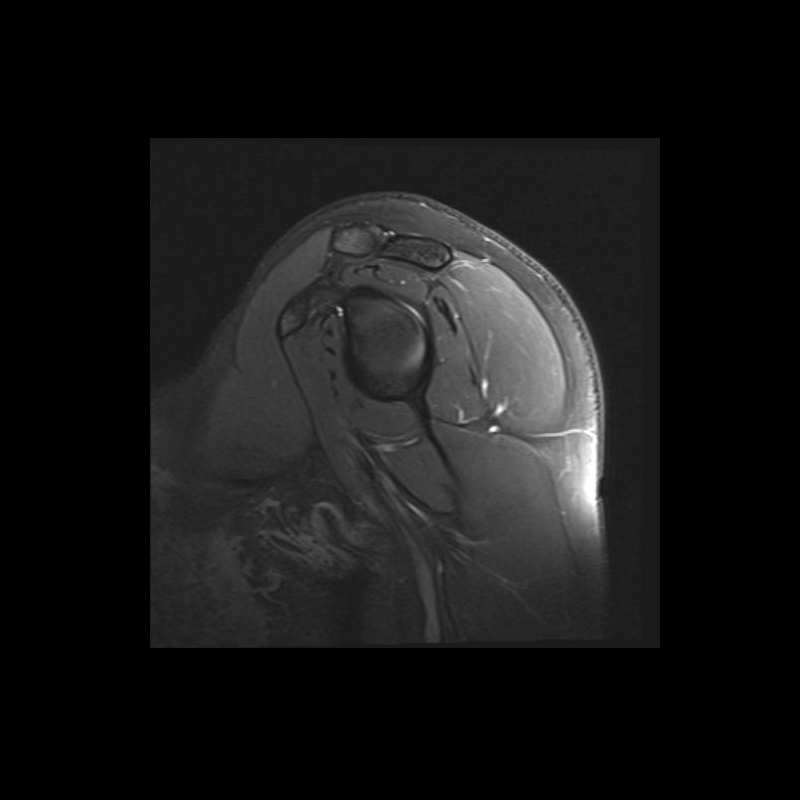

Shoulder MRI Anatomy